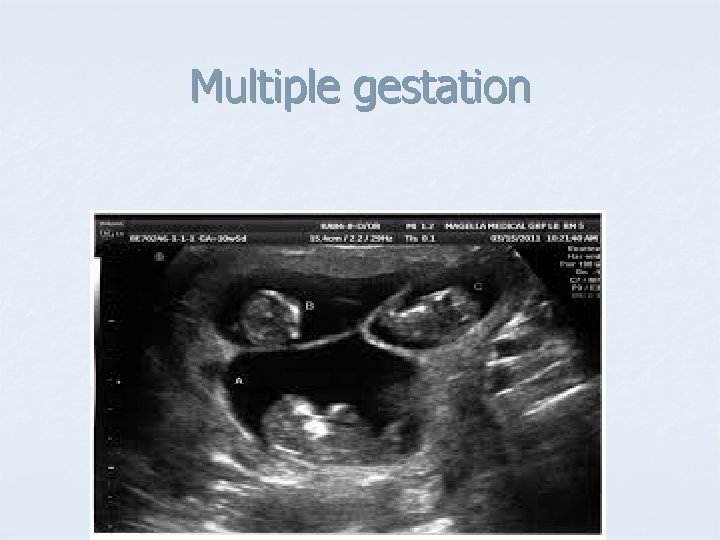

Multiple gestation